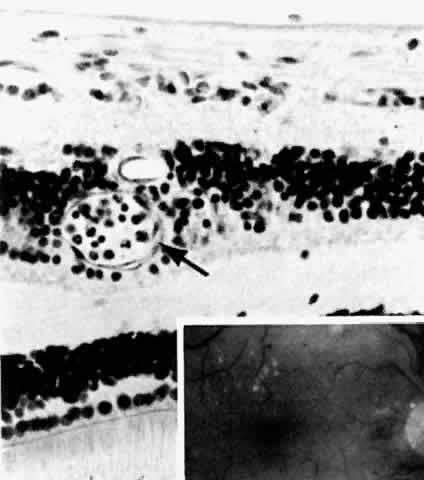

| Patients with diabetes may have tiny pinpoint iris transillumination defects. This

the iris pigment epithelium (Fig. 2; Color Plate 1,* Color Fig. A).18 These vacuoles contain glycogen. Some authors have found that the vacuolization

is transient, and thus related to blood glucose levels prior

to death,19 whereas others have been less convinced of such a relationship.20 See Color Plate 1 for Color Figs. A through G These glycogen vacuoles can rupture when the intraocular pressure is suddenly reduced, resulting in a cloud of pigment granules carried anteriorly in the aqueous fluid. This pigment may then be phagocytosed by the corneal endothelium. The pupils of patients with diabetes often dilate poorly, and the amount of glycogen in the pigment epithelium may correlate to damage to the dilator muscle. Rubeosis iridis is a clinical term for the reddish discoloration imparted by neovascularization of the iris surface. It is associated most frequently with retinal ischemia and neovascularization, and indicates the presence of a diffusible vascular proliferative factor secreted by the retina.21 Initially, the vessels can be quite difficult to see. With more advanced rubeosis, there may be ectropion uveae, an eversion of the posterior iris surface at the pupil margin. The earliest location of the new vessels has been a matter of longstanding debate. They appear at the pupil margin and in the angle virtually simultaneously, subsequently spreading across the iris surface, but gonioscopic examination is required for the vessels to be seen in the angle. In some patients, the vessels do form in the angle before being perceptible at the pupil margin.22 Peripheral anterior synechiae form rapidly after neovascularization of the iris, closing off the trabecular meshwork and giving rise to so-called neovascular glaucoma, which is difficult to treat. In addition, the vessels and associated fibrous tissue can proliferate across the pupil, sequestering it. Particularly in aphakic patients, the vessels can also extend through the pupil and onto the posterior iris surface. Histologically the new vessels are located anterior to the anterior border layer of the iris (Fig. 3, Color Fig. B). They are thin-walled, unlike the normal thick-walled iris stromal vessels. New vessels may be located only at the pupillary margin and in the angle at the iris root, corroborating the clinical finding.18 Scanning electron microscopy has disclosed a thin, transparent layer of myofibroblastic proliferation anterior to the new vessels. This explains the clinical observation that the anterior iris surface appears smoothed out, with loss of the collarette and crypts typically seen on the normal iris surface. Myofibroblasts have contractile properties and thus may be responsible for the angle closure of neovascular glaucoma and also for the eversion of the posterior iris surface at the pupillary margin (Color Fig. C).23 |

For reasons that remain obscure, the basement membrane of the pigment epithelium

of the pars plicata of the ciliary body is thickened in diabetes. The

basement membrane of the nonpigmented epithelium is also thickened, but

this is much more subtle (Fig. 4).18

Arteriosclerotic changes in the choroidal vessels are more common in diabetic patients than in matched nondiabetics. These changes include fibrosis and hyalinization of the media with plaque formation in larger vessels.18 The choriocapillaris shows diffuse thickening of the basement membrane, sometimes to the point of total vascular occlusion. Both pericytes and endothelial cells appear to participate in this process of excess basement membrane synthesis. The obliterated capillaries form eosinophilic nodules that superficially resemble drusen, although they are on the choroidal side of Bruch's membrane. They also resemble the nodules seen in kidneys of patients with diabetic glomerulosclerosis.24 Two patients in Hidayat and Fine's series,24 both less than 30 years old and who had not been treated with photocoagulation, showed peripheral subretinal neovascularization, one near the equator and one near the ora. The significance of this finding is uncertain. |